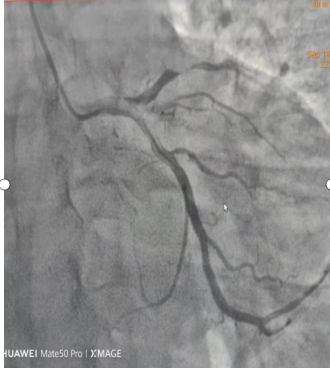

一张心梗造影,血管因堵塞不太清晰。

9月19日,47岁的市民刘先生(化名)与朋友就餐后返回家中,随即出现胸痛、胸闷、汗出,朋友将他送到市中医院急诊科,被初步诊断为急性广泛前壁心肌梗死。此时,刘先生已丧失意识,心室出现颤动。医生立即启动绿色通道,为他进行心肺复苏、心脏电除颤,并为其介入治疗,打通了他闭塞的冠状动脉血管,才使他转危为安。